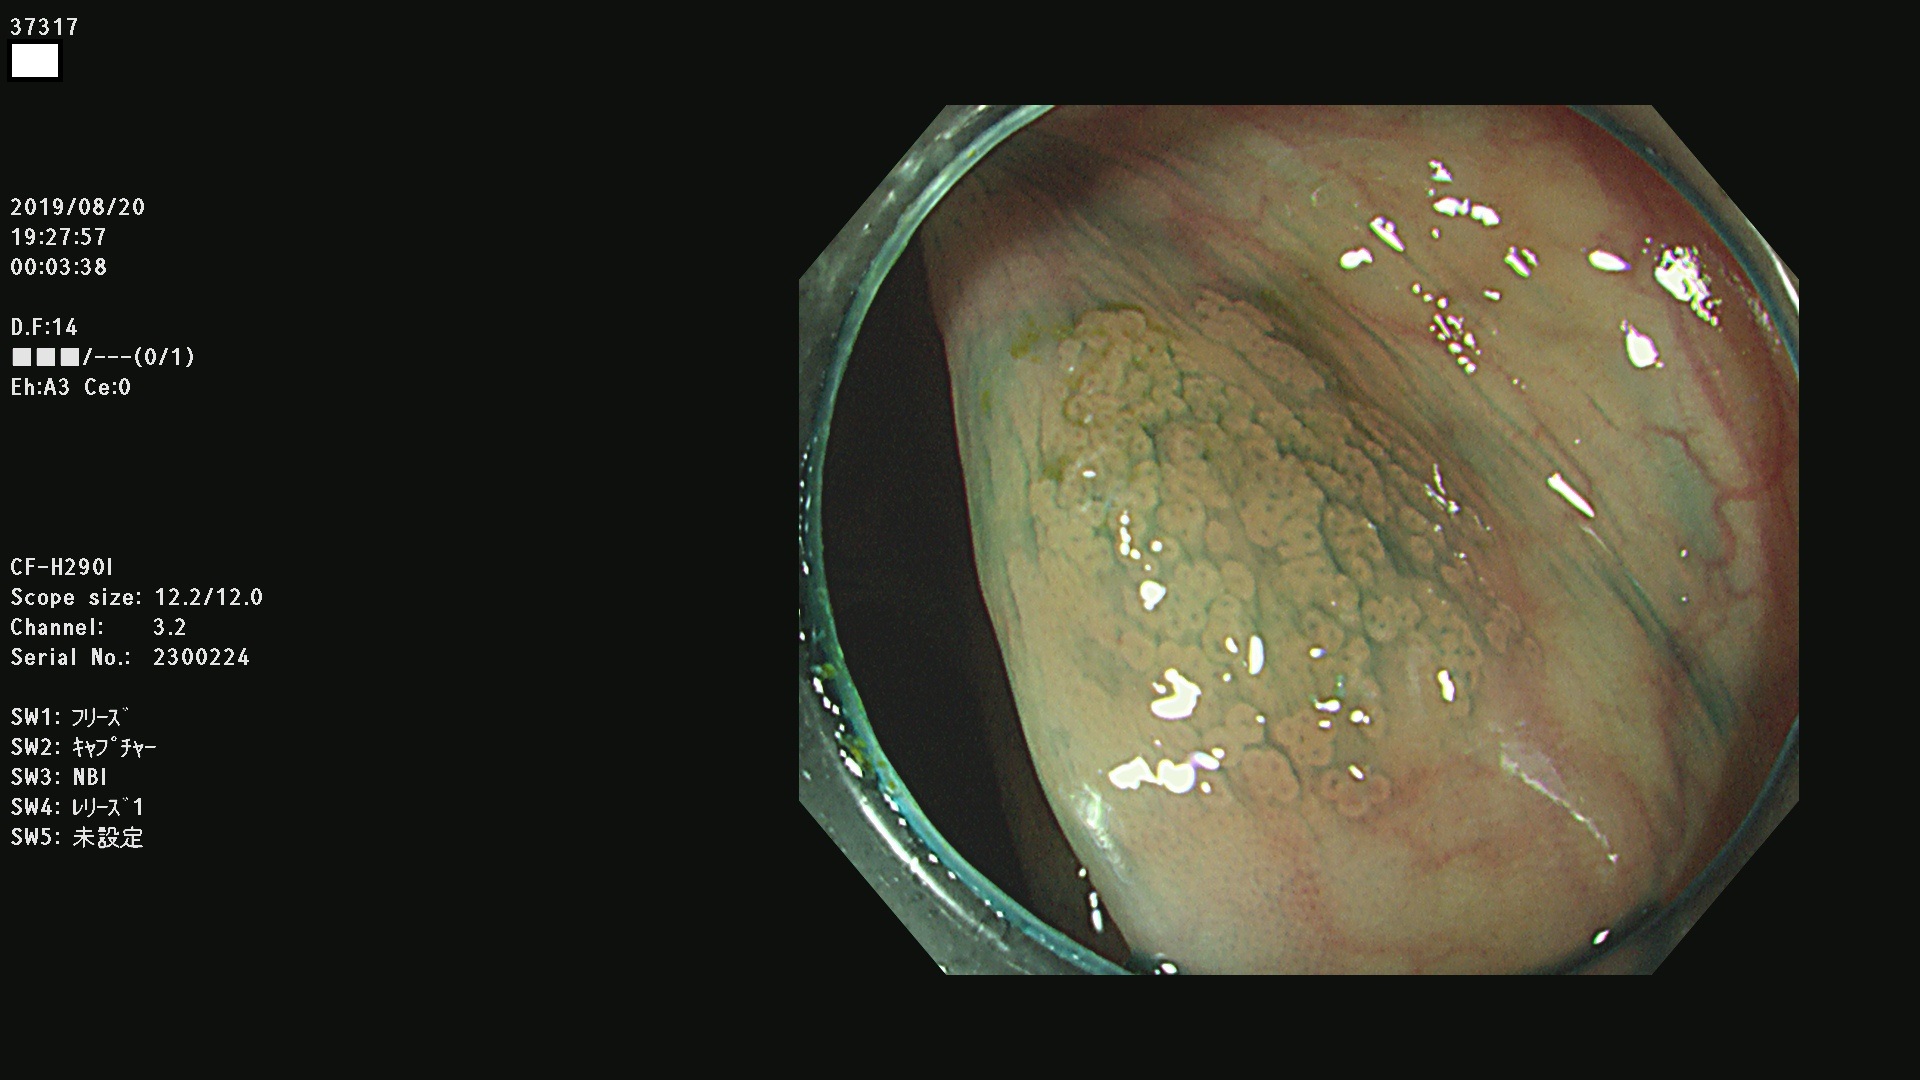

37300(SSAPのみ) 37301 37303 37304 37306 37307 37308 37309 37312 37313 37315(SSAPのみ) 37316 37317(SSAPのみ) 37319 37321(SSAPのみ) 37322 37323 37324 37325 37326 37328(SSAPのみ) 37329 37330 37331 37332(SSAPのみ) 37333 37334 37336 37337 37338 37340 37342 37343(SSAPのみ) 37344 37345 37346 37347 37348 37352(SSAPのみ) 37353 37354 37355 37356 37358 37360 37361(SSAPのみ) 37362 37363 37366 37367 37369 37370 37371 37372(SSAPのみ) 37375 37376 37377 37380 37381(SSAPのみ) 37382 37383 37384 37385(SSAPのみ) 37386 37387 37388 37389 37390 37392(SSAPのみ) 37393 37394 37395 37396(SSAPのみ) 37397 37398(SSAPのみ) 37399

発見困難で危険性の高い平坦型病変(上記100名より抽出) )